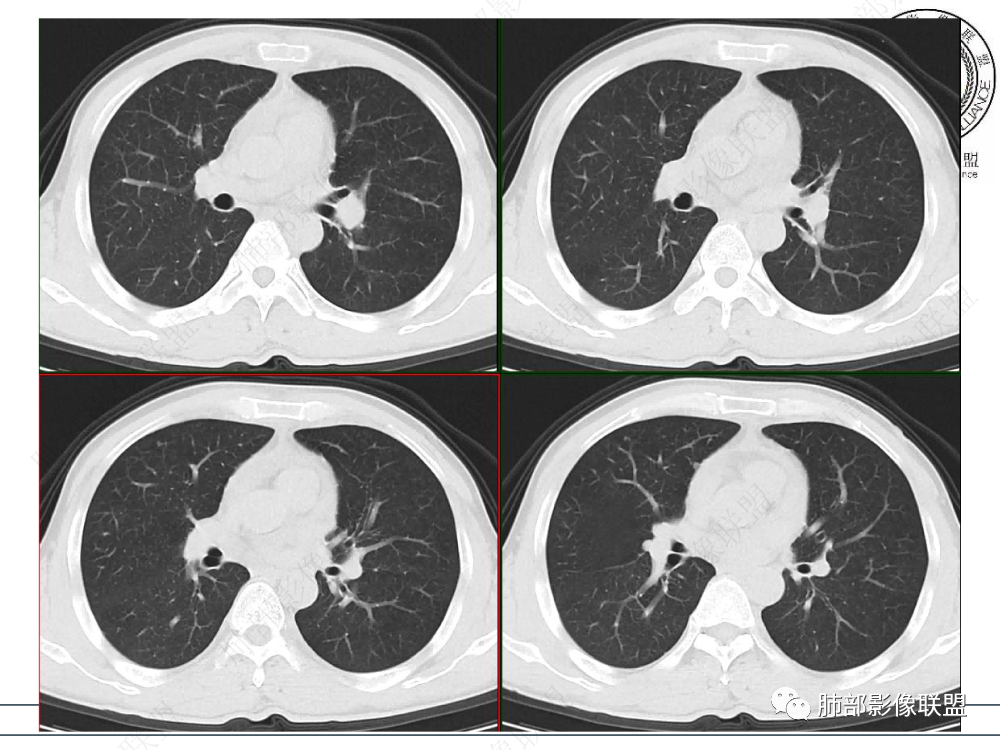

1.临床资料:中老年男性,病史较长-8个月,主诉胸痛,实验室资料:乳酸脱氢酶(LDH)升高。

2.影像表现:前上纵隔较大肿块,密度不均,形态不规则,边界不清,有结节样突起,脂肪间隙显示不清。病灶侵犯左无名静脉及上腔静脉,其中左无名静脉闭塞(胸背部侧支循环明显,亦表明回流受阻)。增强后轻中度不均强化。坏死边界欠清晰。可见心包积液,提示心包受侵犯。右侧上叶及纵隔胸膜下结节影,疑胸膜肺转移可能。胸骨柄后缘皮质不完整,疑骨质破坏(未提供骨窗及矢状位图像)。左锁骨上可见肿大淋巴结。

胸腺癌:病灶边界不清,骨骼及血管受侵破坏,胸膜、肺及心包受侵转移等首先想到胸腺癌。胸腺癌最常见病理类型为鳞癌,占70-79%。预后较差,50-65%初诊时伴肺转移,极少伴重症肌无力。影像:胸腺鳞癌形态不规则,易坏死,范围大,坏死区边缘常模糊。

胸腺瘤:胸腺瘤大多边界较清楚。边界模糊或心包侵犯可见于B3型胸腺瘤和癌,但胸腺瘤罕见远处转移、淋巴结转移和纵隔大血管侵犯。

淋巴瘤:体积常较大,常见常在10cm以上,相对低密度结节样堆砌感比较明显,对待骨骼、血管等结构相对“温和”,所谓“血管漂浮”、“肉包骨”则较为常见。病理类型几乎只见于:经典HD、大B细胞淋巴瘤,前驱T淋巴母细胞瘤。实验室检查LDH可升高。初诊时罕见钙化,罕见胸膜受侵。有坏死也常常边界清楚或呈囊变样外观,可伴纵隔、锁骨上淋巴结肿大。